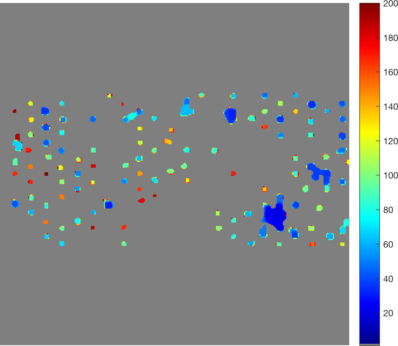

• [ZXSE07] Noha El Zehiry, Steve Xu, Prasanna Sahoo, and Adel Elmaghraby. Graph cut optimization for the Mumford-Shah model. In VIIP ’07 The Seventh IASTED International Conference on Visualization, Imaging and Image Processing, pages 182–187, 2007.